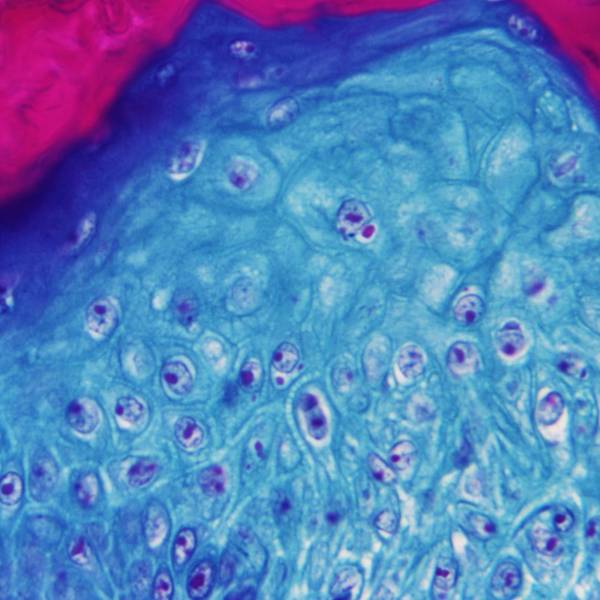

Imagen ampliada con un microscopio de una muestra de piel de un mono infectado con el virus de la viruela del mono, cedida por el "Center for Disease Control and Prevention". EFE( )